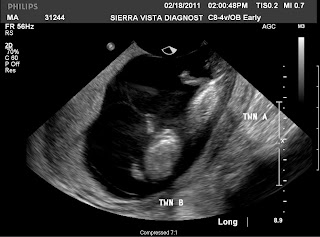

So the Ultra Sound reviled TWINS. I'm still in shock. This changes my perspective a little, how much weight gain, how many calories I need. Mostly I need to adjust my perspective of my weight gain.

Oh my goodness- TWINS